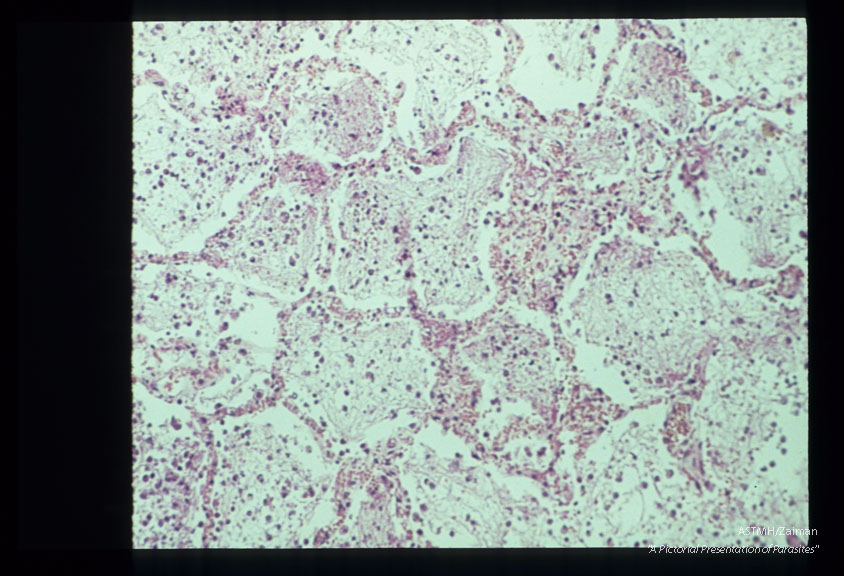

Pneumonia. The characteristic foamy alveolar exudate is well seen.

Pneumocystis carinii

Description: Pneumonia. The characteristic foamy alveolar exudate is well seen.